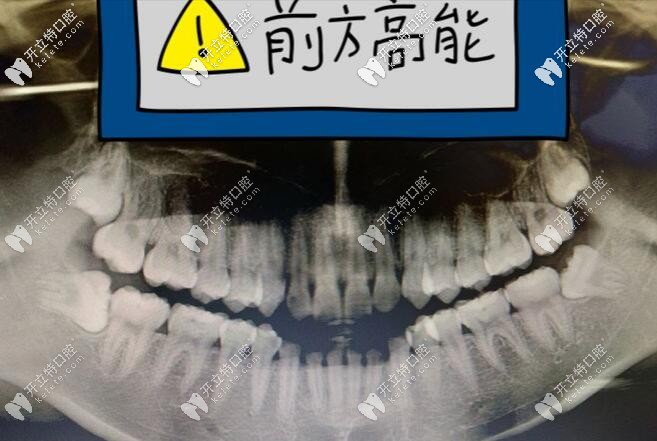

所以這次拔牙還是想找位好醫(yī)生,直接找的占醫(yī)生,本身我的牙齒屬于那種阻生牙齒,所以醫(yī)生也說了,拔起來難度不低的,一方面給我講了牙齒的癥狀,一方面還寬慰我。

口腔CT片